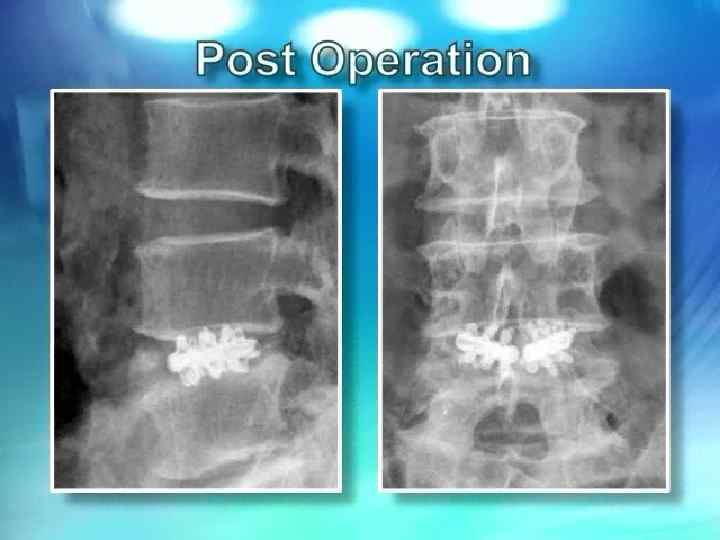

Операция Юмашева - Фурмана

Синдром смежного уровня Развитие патологических изменений в позвоночном сегменте, смежном с уровнем фиксации получило обозначение: “Cиндром смежного уровня”

Синдром смежного уровня 2004 2005 2006 Применение жесткой стабилизации одного или нескольких позвоночных сегментов приводит к серьезным изменениям в биомеханике позвоночника и перераспределению нагрузок